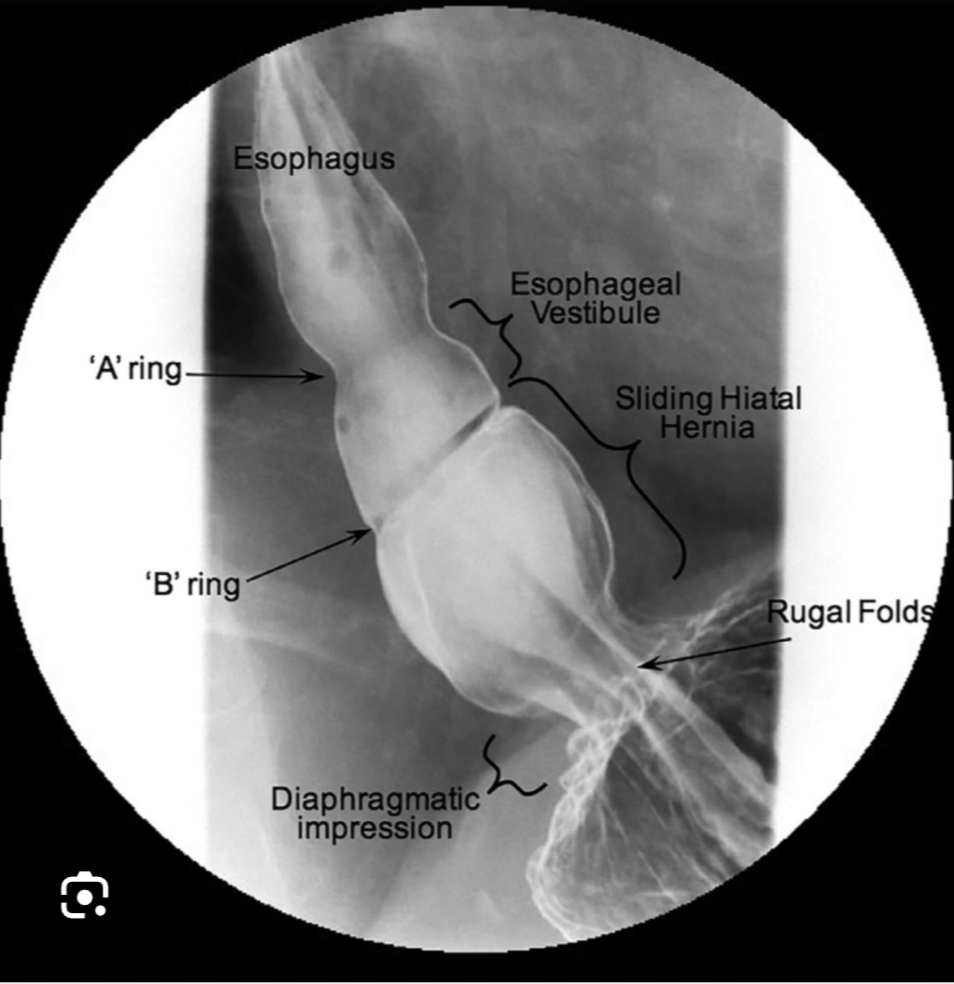

• most common type, accounts for >90% of cases. Involves a sliding movement of the gastroesophageal junction (GEJ) above the diaphragm alongside a portion of the stomach. Clinically, it is often associated with gastroesophageal reflux disease (GERD).

3 - Sliding Hiatus Hernia

Classed as a type I HH

3 - barium swallow

Gives information about the size, type and any associated complications of the HH